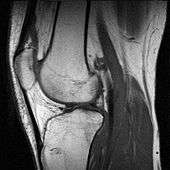

In addition, variants of false color such as pseudocolor (see discussion), density slicing (see discussion), and choropleths (see discussion) are used for information visualization of either data gathered by a single grayscale channel or data not depicting parts of the electromagnetic spectrum (e.g. elevation in relief maps or tissue types in magnetic resonance imaging).

A pseudocolor image (sometimes styled pseudo-color or pseudo color) is derived from a grayscale image by mapping each intensity value to a color according to a table or function.[7] Pseudo color is typically used when a single channel of data is available (e.g. temperature, elevation, soil composition, tissue type, and so on), in contrast to false color which is commonly used to display three channels of data.[4]

Depending on the table or function used and the choice of data sources, pseudocoloring may increase the information contents of the original image, for example adding geographic information, combining information obtained from infrared or ultra-violet light, or other sources like MRI scans.[8]